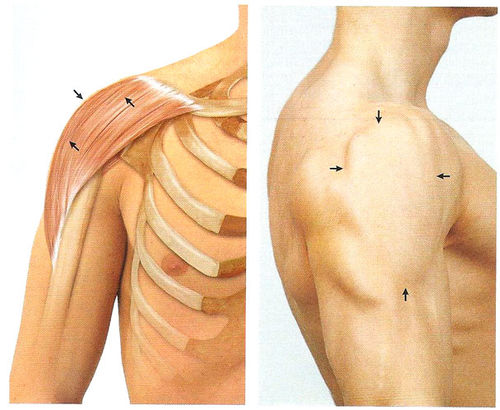

Фотографии поддельтовидной мышцы плечевого сустава